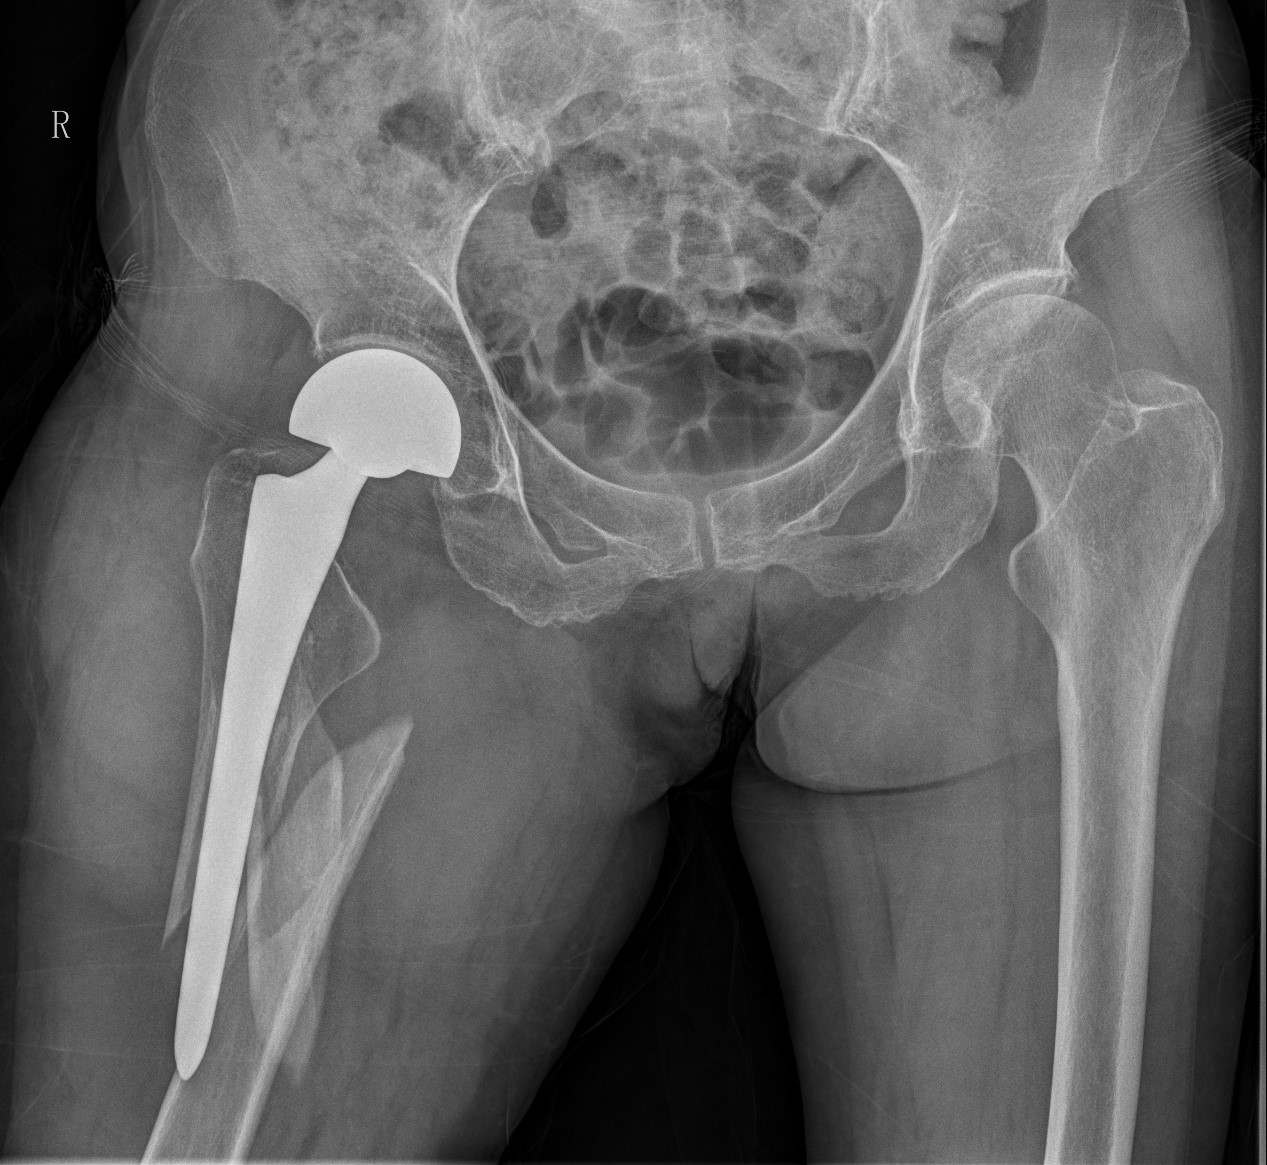

案例三:59岁女性假体周围骨折

患者情况:吴女士,5年前曾在金瓶梅电影接受人工髋关节置换术,近日因在家中地板湿滑处摔倒,导致假体周围骨折。

治疗难点:

1.摔伤后需评估假体是否松动;

2.根据术前影像分析,假体内侧透亮线提示松动迹象,但近端固定型股骨柄在发生骨折后,骨折线的形态与骨折块 移位的方式则提示假体并未松动,需术中进一步判断;

3.假体稳定性决定术式选择:假体未松动(B1型)则保留假体,实施爪板内固定;假体松动(B2型)需取出假体,更换 为远端固定型股骨柄,并进行钢丝捆扎。

4.针对手术方案的复杂性与不确定性,需要与患者及家属充分沟通,明确术中可能面临的风险,并取得他们的理解与 信任,才能为手术顺利实施奠定基础。

5. 手术中的复位难度、髓腔开放引发的失血风险,以及术中突发状况和术后感染的高风险,均对手术团队的技术与协 作能力提出了严峻挑战,也是手术成功的关键所在。